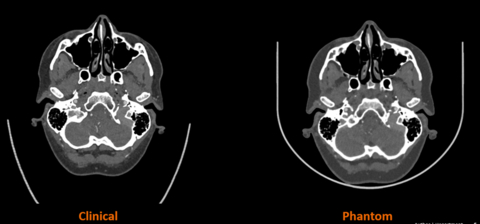

A critical tool in medical imaging and an almost universal resource in hospitals worldwide, CT phantoms are specialized devices used to evaluate and ensure the performance of CT scanners. Designed to simulate certain characteristics of the human body, phantoms enable the assessment of various core metrics, including radiation dose and image quality, aiding calibration and safeguarding consistent scanner performance. The joint development leverages Stratasys’ PolyJet™ technology in combination with its unique RadioMatrix™ technology, and Siemens Healthineers’ advanced algorithm aimed at translating scanned patient images into specific material characteristics with radiopacity of human anatomy. The solution will allow for tailored phantom manufacturing and the creation of ultra-realistic human anatomy characteristics with complete radiographic accuracy of patient-specific pathology not previously possible.

Beginning with the manufacturing of 3D printed phantoms for smaller-scale anatomies of the head and neck region, the research will involve the production of progressively larger and complex anatomies – leading up to the Phase One endpoint of 3D printing a heart model and of an entire human torso with complete radiographic accuracy.